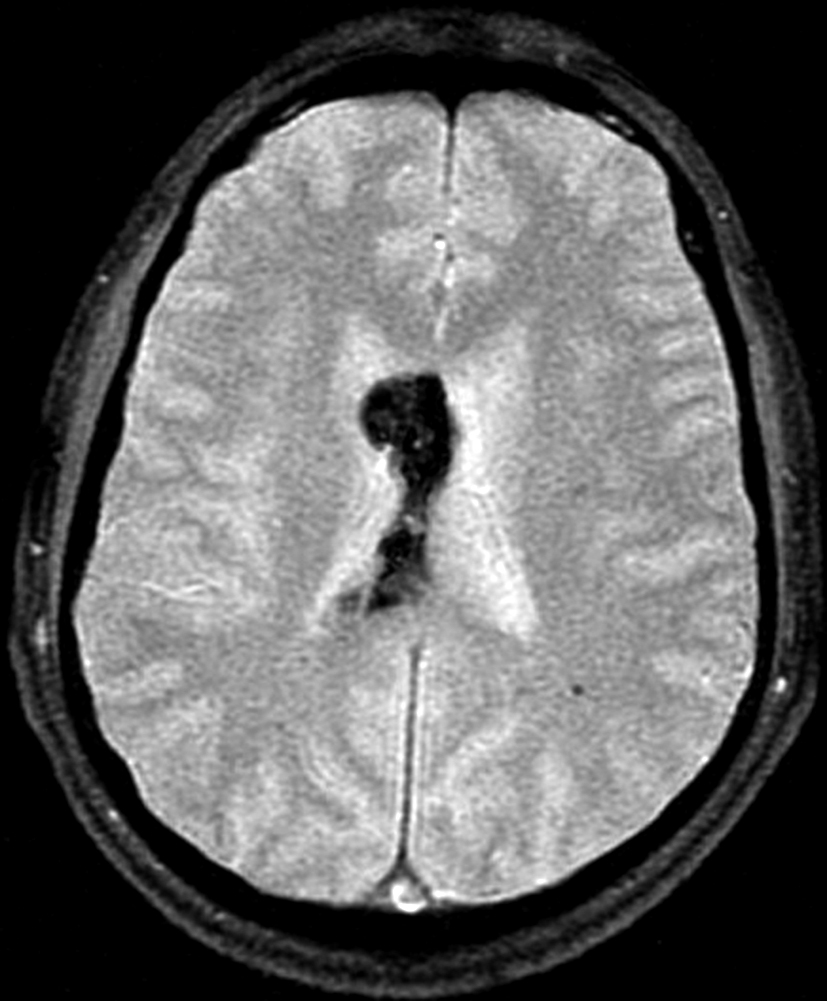

Se efectúa un control imagenológico al año del diagnóstico mediante una TC sin y con contraste (Figura 5 – A y B), donde se evidencia la lesión sin cambios significativos en cuanto a su tamaño y características.

Figura 5

a y b) Cortes axiales de TC sin y con contraste intravenoso. Control tomográfico al año del estudio inicial, no se observan cambios significativos de la lesión.